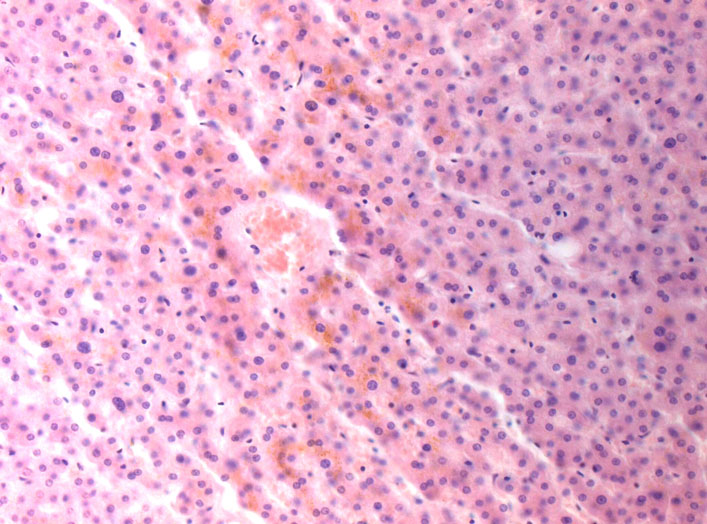

Микрофотографии гистологии глиобластомы головного мозга